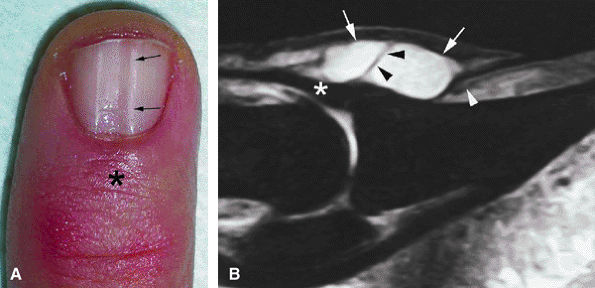

-

Pain (the main symptom)

A slight lifting of the dorsal aspect of the distal phalanx

Distal onycholysis, sometimes emerging beneath the free edge of the nail plate

Nail failure, which may cause surface erosion leading to infection mimicking an ingrown nail or a melanoma222

distal phalanx, but this distinction may be difficult to appreciate (Fig. 11.92).223,224 Since the treatment for both entities is surgical excision, radiographic evaluation is sufficient for preoperative evaluation.